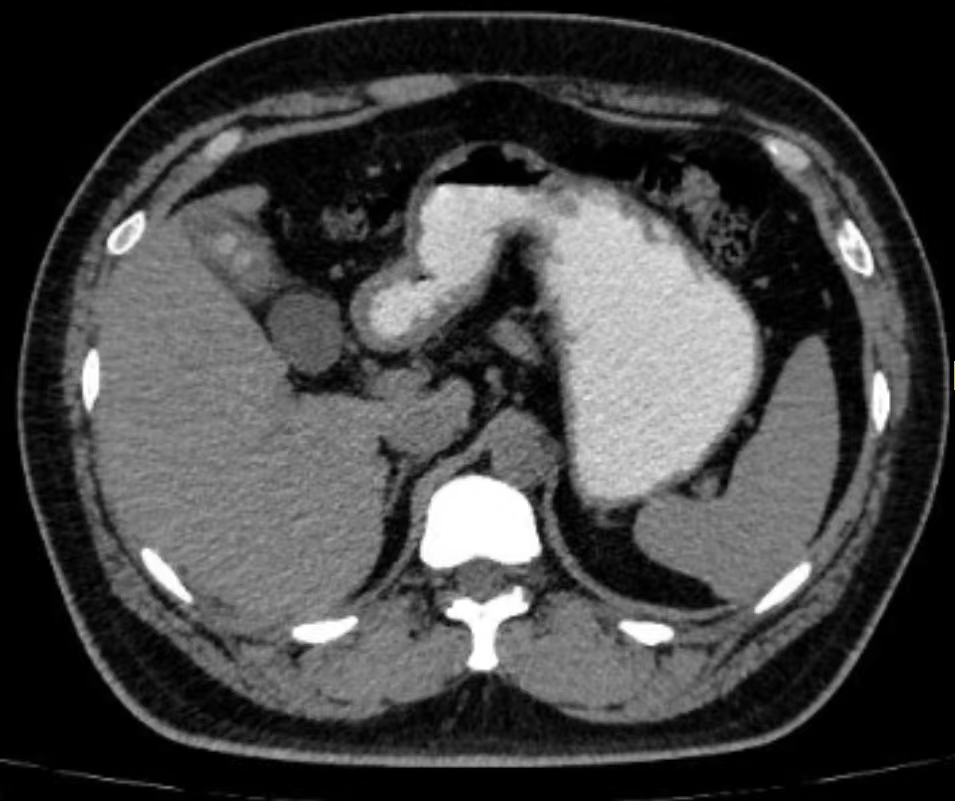

患者,青年男性,查体发现胆囊壁增厚已有3年。医院就诊:CT显示胆囊体部隔膜形成,胆囊底部胆汁引流不畅,胆囊结石形成,胆囊壁炎性增厚。胆囊结石、胆囊壁>3mm、胆囊萎缩、胆囊畸形、瓷化胆囊是胆囊癌的危险因素,应及时行胆囊切除术。